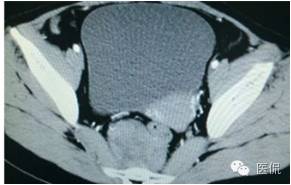

增强动脉期(CT值31HU)